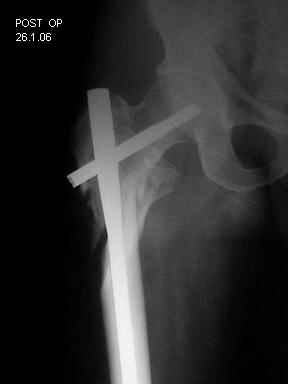

Re: Severely comminuted Trochenteric #

Few days ago I have posted an x-ray of severely comminuted Trochenteric # of Lt. Femur with sub-trochenteric extension of a male patient aged 65 years for opinion of fixation. Eight of you have kindly replied........

I choose Long Gamma Nailing and did it on 24.1.2006.

Now posting the post op x-rays for all of yours comments please. Don't hesitate to criticize me.